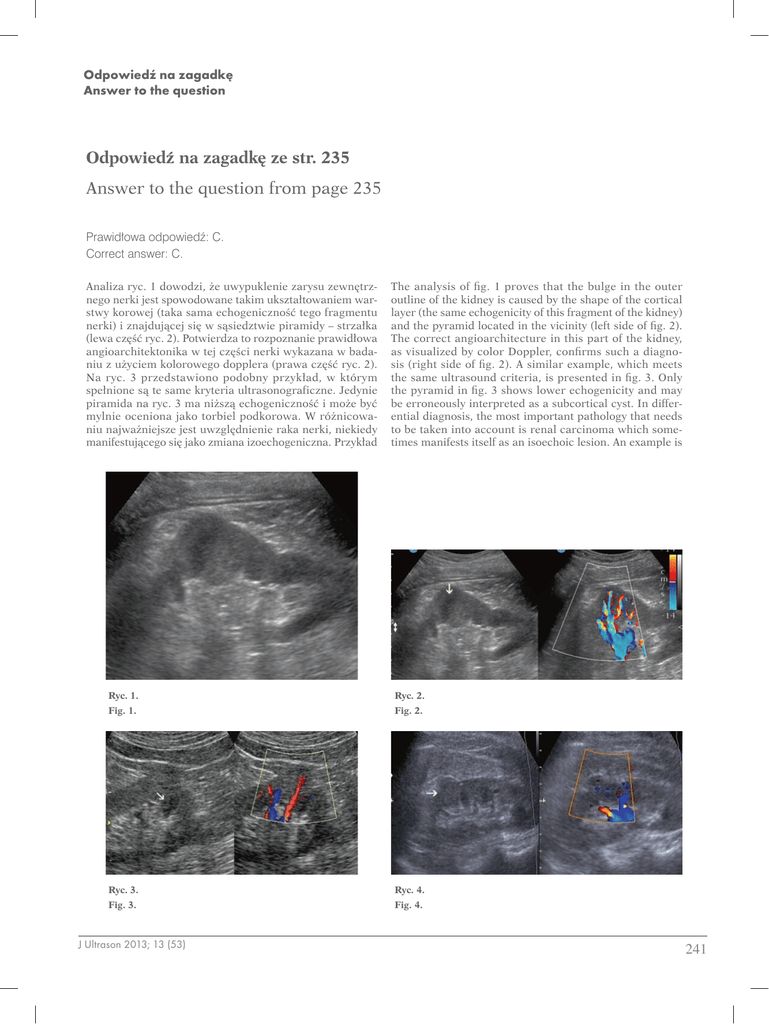

The analysis of fig. 1 proves that the bulge in the outer

outline of the kidney is caused by the shape of the cortical

layer (the same echogenicity of this fragment of the kidney)

and the pyramid located in the vicinity (left side of fig. 2).

The correct angioarchitecture in this part of the kidney,

as visualized by color Doppler, confirms such a diagnosis (right side of fig. 2). A similar example, which meets

the same ultrasound criteria, is presented in fig. 3. Only

the pyramid in fig. 3 shows lower echogenicity and may

be erroneously interpreted as a subcortical cyst. In differential diagnosis, the most important pathology that needs

to be taken into account is renal carcinoma which sometimes manifests itself as an isoechoic lesion. An example is